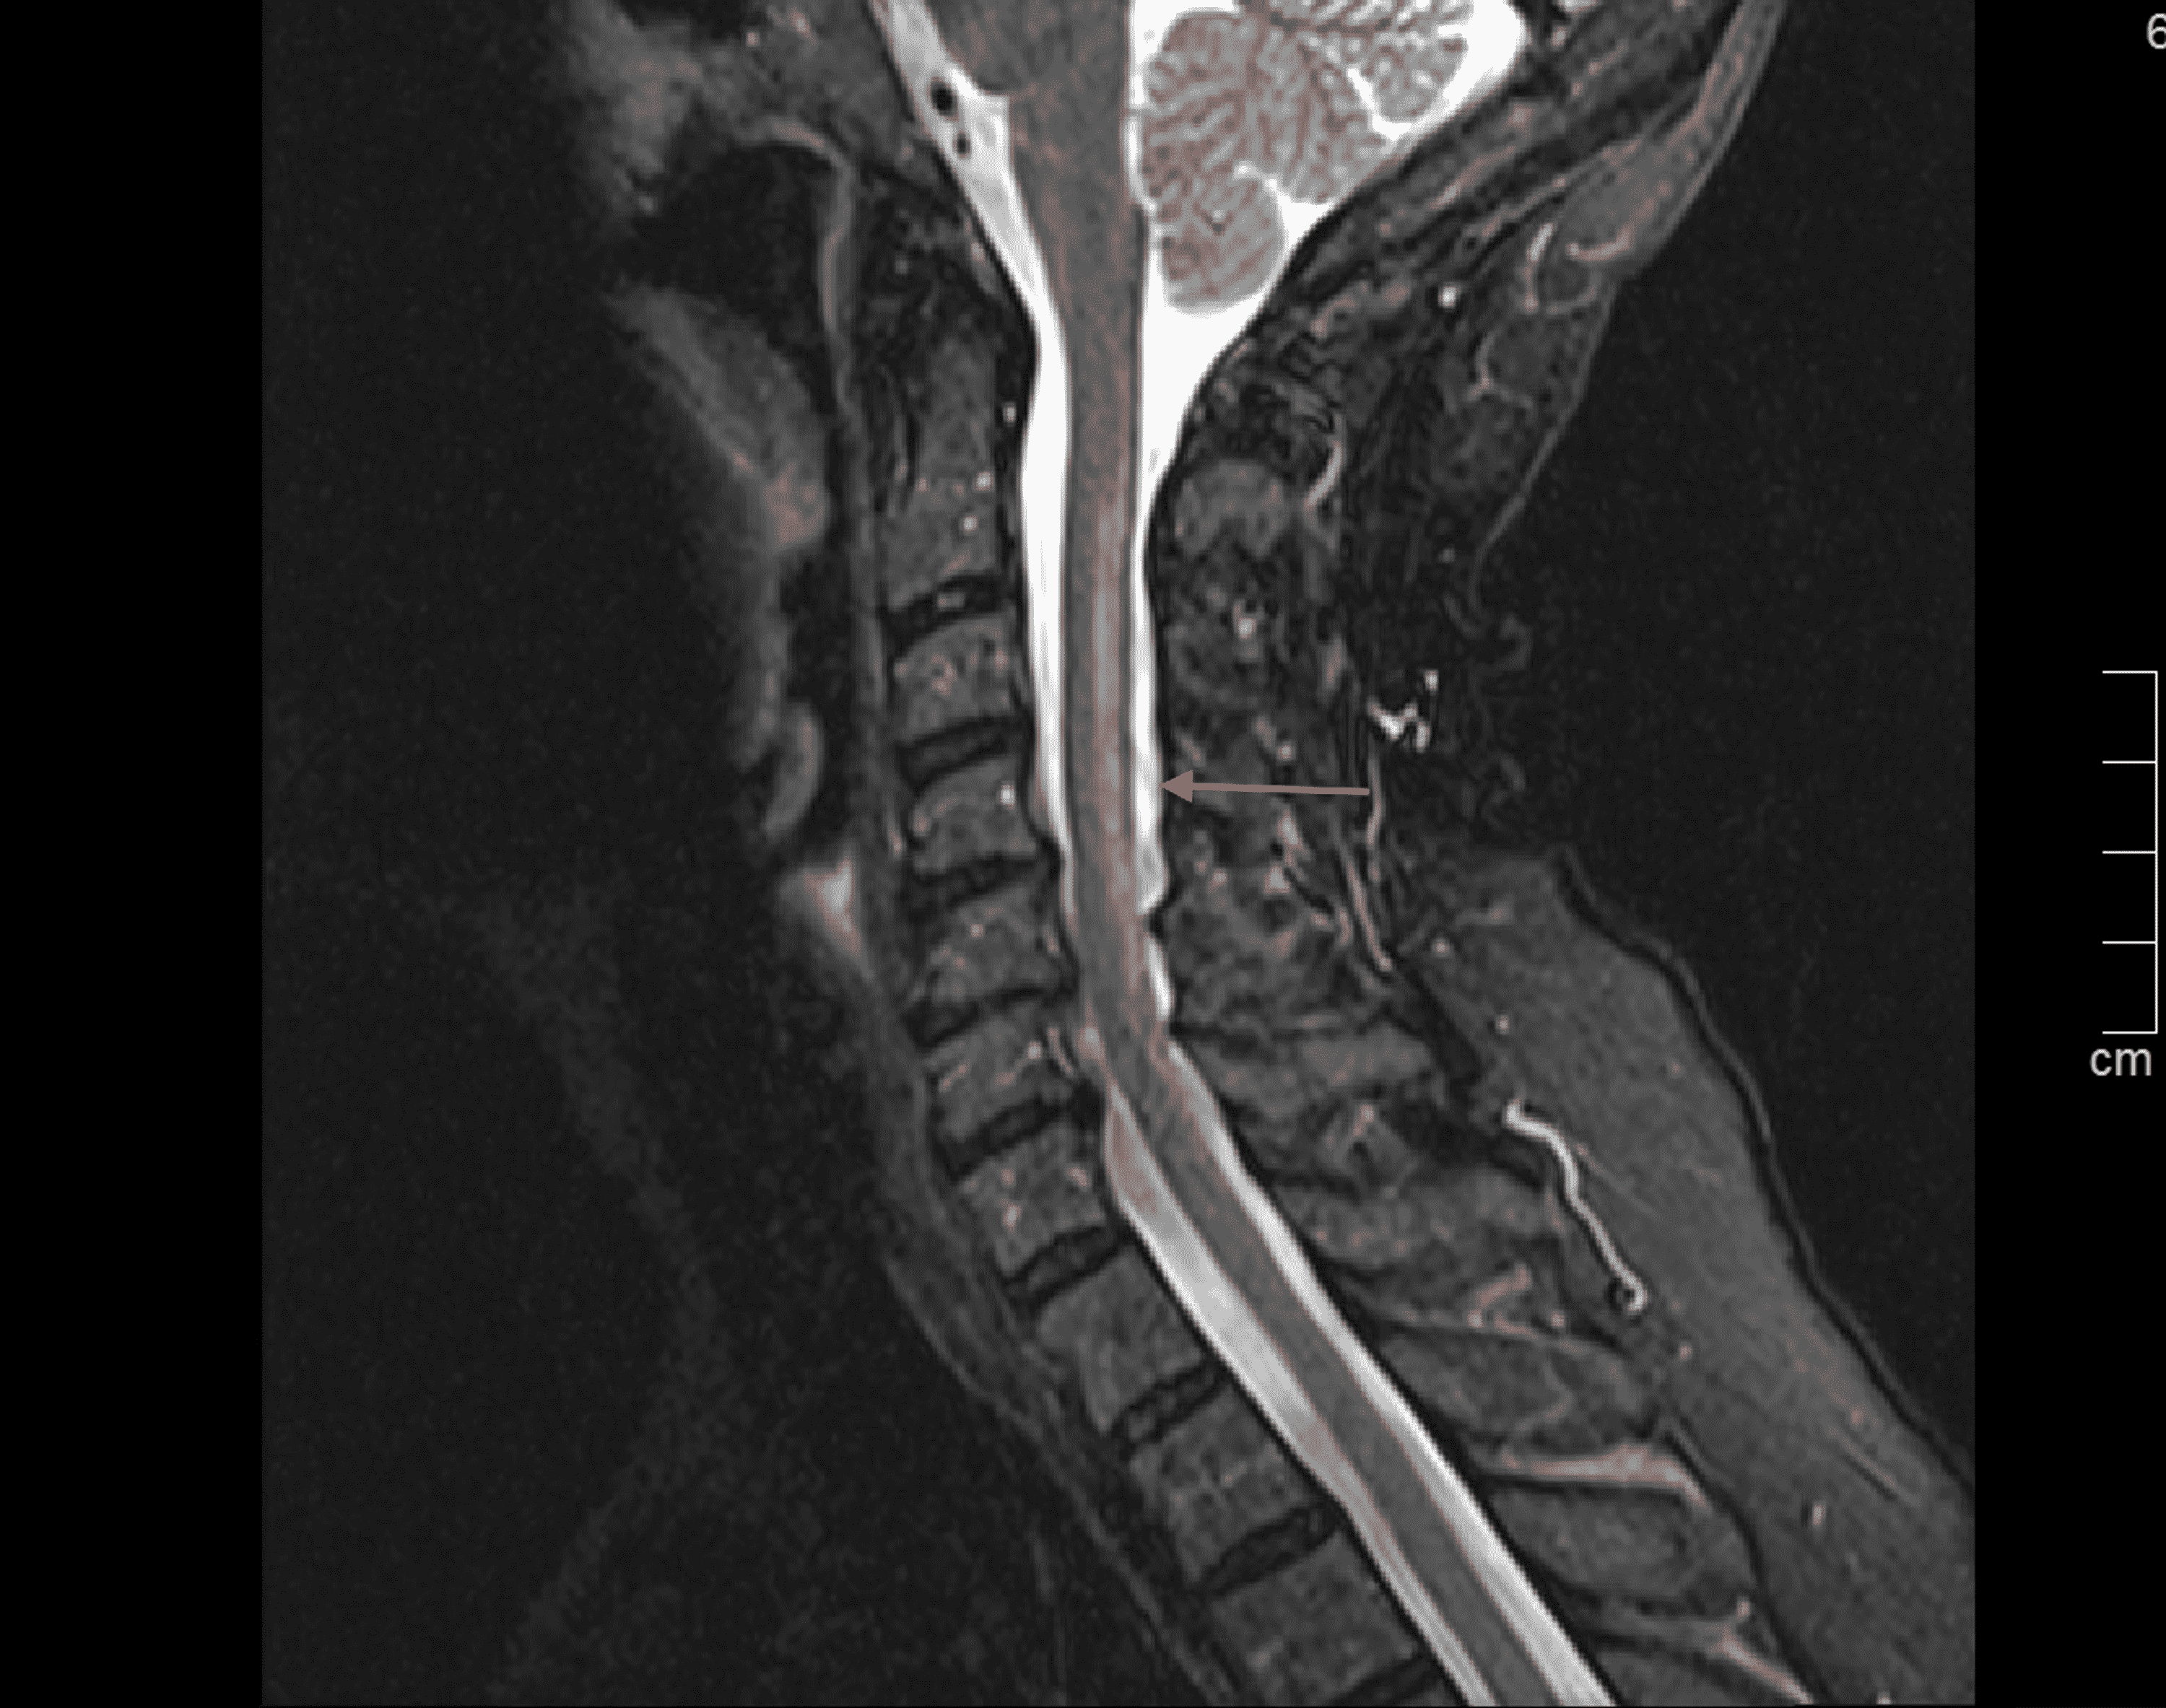

Cureus Copper Deficiency Myeloneuropathy Following RouxenY Gastric Copper Deficiency Roux En Y copper deficiency can cause hematological abnormalities with or without neurological complications. Procedures that are both restrictive and. overall, copper deficiency occurs infrequently with bariatric surgery. this clinical observation describes a patient who experienced gait disturbances, lower extremity weakness, and neuropathy. Copper Deficiency Roux En Y.